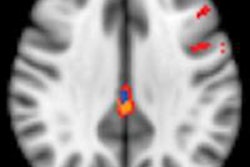

ASL images at baseline for patients with chronic low back pain showed a stronger connectivity between the medial prefrontal cortex of the brain and a network of brain areas known as the default mode network, compared with the healthy group.

Results also showed that the back pain patients experienced less pain when there was a greater connection between the default mode network and the medial prefrontal cortex, which, the authors noted, suggests that the connection may be a pain-protective mechanism.

In addition, the ASL images showed that the connectivity between the medial prefrontal cortex and the default mode network decreased after the assigned movements in back pain patients, but not in the control subjects.